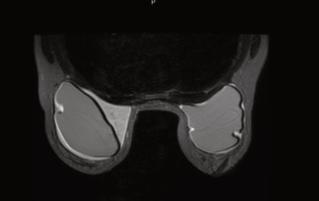

Larelaciónentrelaobesidadylasenferme‐dadescardiovascularesesinnegable.Laobe‐sidadpuededesencadenarunaseriedeefec‐tosadversosenelsistemacardiovascular,au‐mentandoelriesgodedesarrollarcondiciones comolacardiomegalia,ladisfuncióndiastó‐licaylacardiopatíaisquémica.

Cardiomegalia. Laobesidadpuedellevaralagran‐damientodelcorazón,unacondiciónconocida comocardiomegalia.Estoponeunacargaadicio‐nalenelcorazónypuedellevaraproblemasde bombeoineficienteydisfuncióncardíaca.

Disfuncióndiastólica. Lacapacidaddelco‐razónparallenarsedesangreadecuadamente durantelarelajación,conocidacomofunción diastólica,puedeversecomprometidaenper‐sonasconobesidad.Estopuedeconducira unadisfuncióndiastólica,queesunfactorde riesgoparalainsuficienciacardíaca.

Cardiopatíaisquémica. Laobesidadaumenta elriesgodeacumulacióndeplacaenlas arterias,loquepuedellevaralacardiopatía isquémica,unacondiciónenlaqueelflujo sanguíneoalcorazónsevecomprometido,au‐mentandoelriesgodeunataquecardíaco.